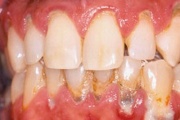

Krooniline parodontiit

Krooniline parodontiit on mikroobide poolt põhjustatud hammaste tugikudede põletik, mille tulemusena tekib progresseeruv alveolaarluu (nähtav röntgenograamil) ja periodontaalligamendi destruktsioon, igemetaskute moodustumine, igeme retsessioon või mõlemad kahjustused kombineeritult. Loe edasi »

Sümptomid:

- igemed veritsevad (19)

- igemed punetavad (21)

- ige on paistes (mädapunn)

- igemed on tursunud/vohavad (17)

- puudulik suuhügieen (5)

- igemepealne hambakivi (5)

- igemealune hambakivi (4)